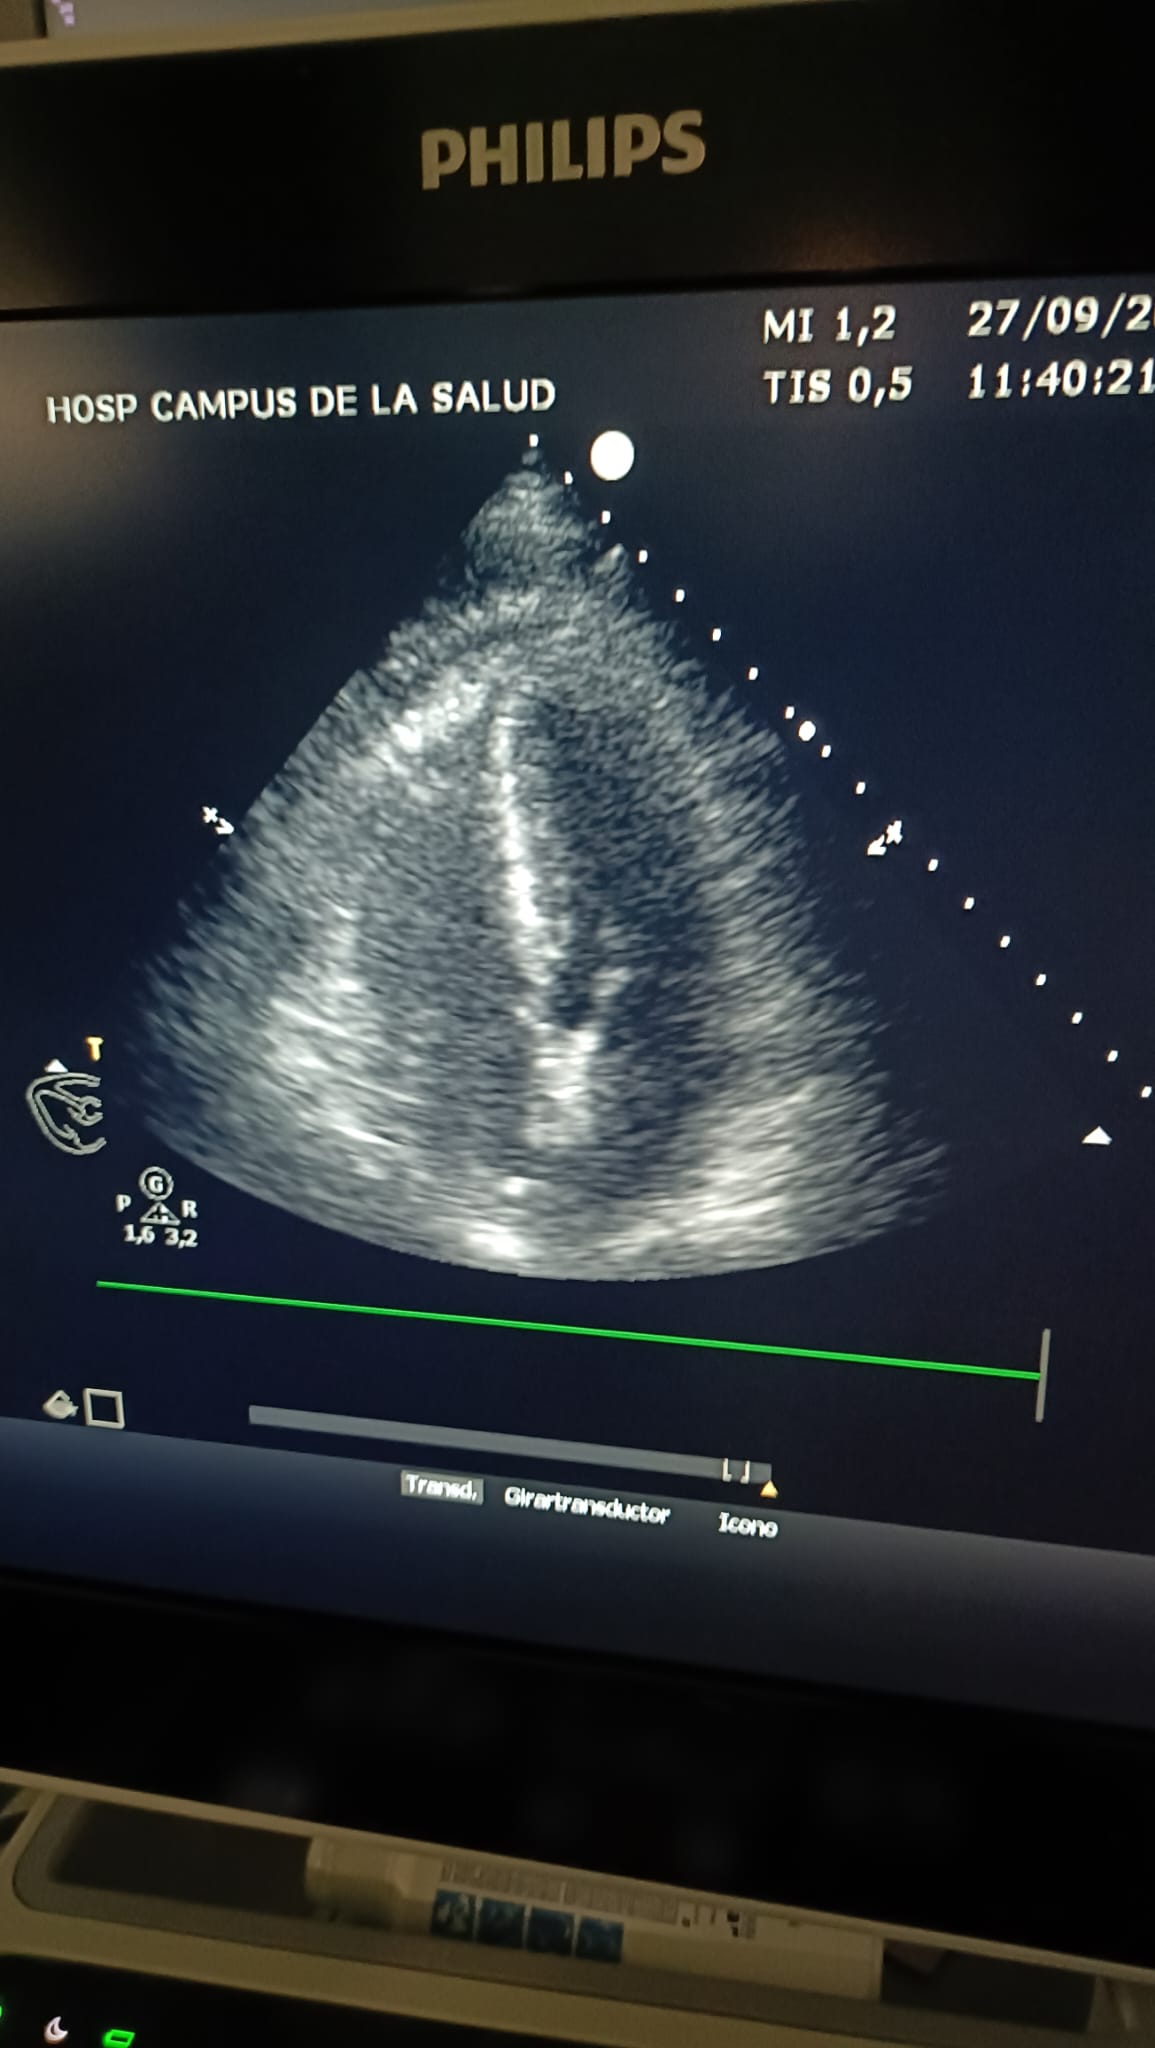

Evaluación visual: normal

IVT: 25.3

Relación E/A: 0.821

Relación E/E' lateral: 6.76

TAPSE: 24.6

Imágenes de Ecocardiografía